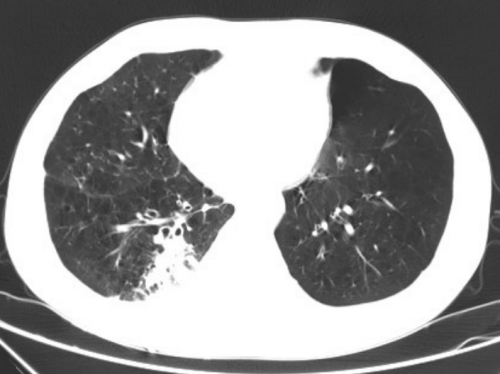

术后三天结节部位坏死、炎性水肿改变

杨继承解释,肺结节微波消融是在肺结节的局部形成高温,使组成肺结节的细胞在高温作用下出现变性、坏死,达到治疗的作用,是肺部结节消融方式的一种。它比微创手术损伤更小,不需要全身麻醉,局部麻醉即可,使病人在治疗过程中,受到的损伤小,且疼痛症状轻微、恢复迅速,手术的可重复性很强,并发症也较少。通常治疗后2-3天,患者各系统的脏器功能基本上能恢复到治疗前的水平,可以出院,所以肺部微波消融术对肺功能保护和良好的局部控制效果,让其可以成为很多因各种原因而无法接受手术治疗的人群的备选治疗选择。